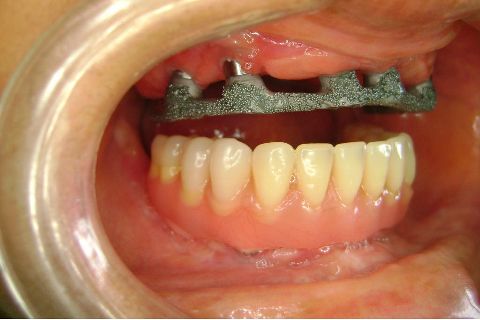

FASE PROTÉTICA DA REABILITAÇÃO EM MAXILA ATRÓFICA...incluindo a reabertura, instalação dos minipilares e PTR provisória reembasada sobre os cilindros de proteção.